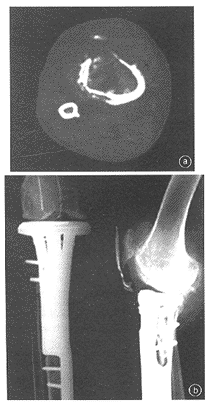

目前此组患者中尚未发现人工关节折断与松动下沉等并发症。在存活超过5年的7例患者中有2例做了截肢术,剩下的5例包括2例生物固定式胫骨上端假体,2例铰链式膝关节,1例人工肘关节,功能均较好。尤以我院自行研制的生物固定式胫骨上端假体功能最好,膝关节稳定,伸膝力接近5级,不痛,伸屈活动0°~130°,步态基本正常(图1)。

a术前CT片b肿瘤切除、生物固定式

图1右胫骨近端骨肉瘤胫骨上端假体置换术后5年